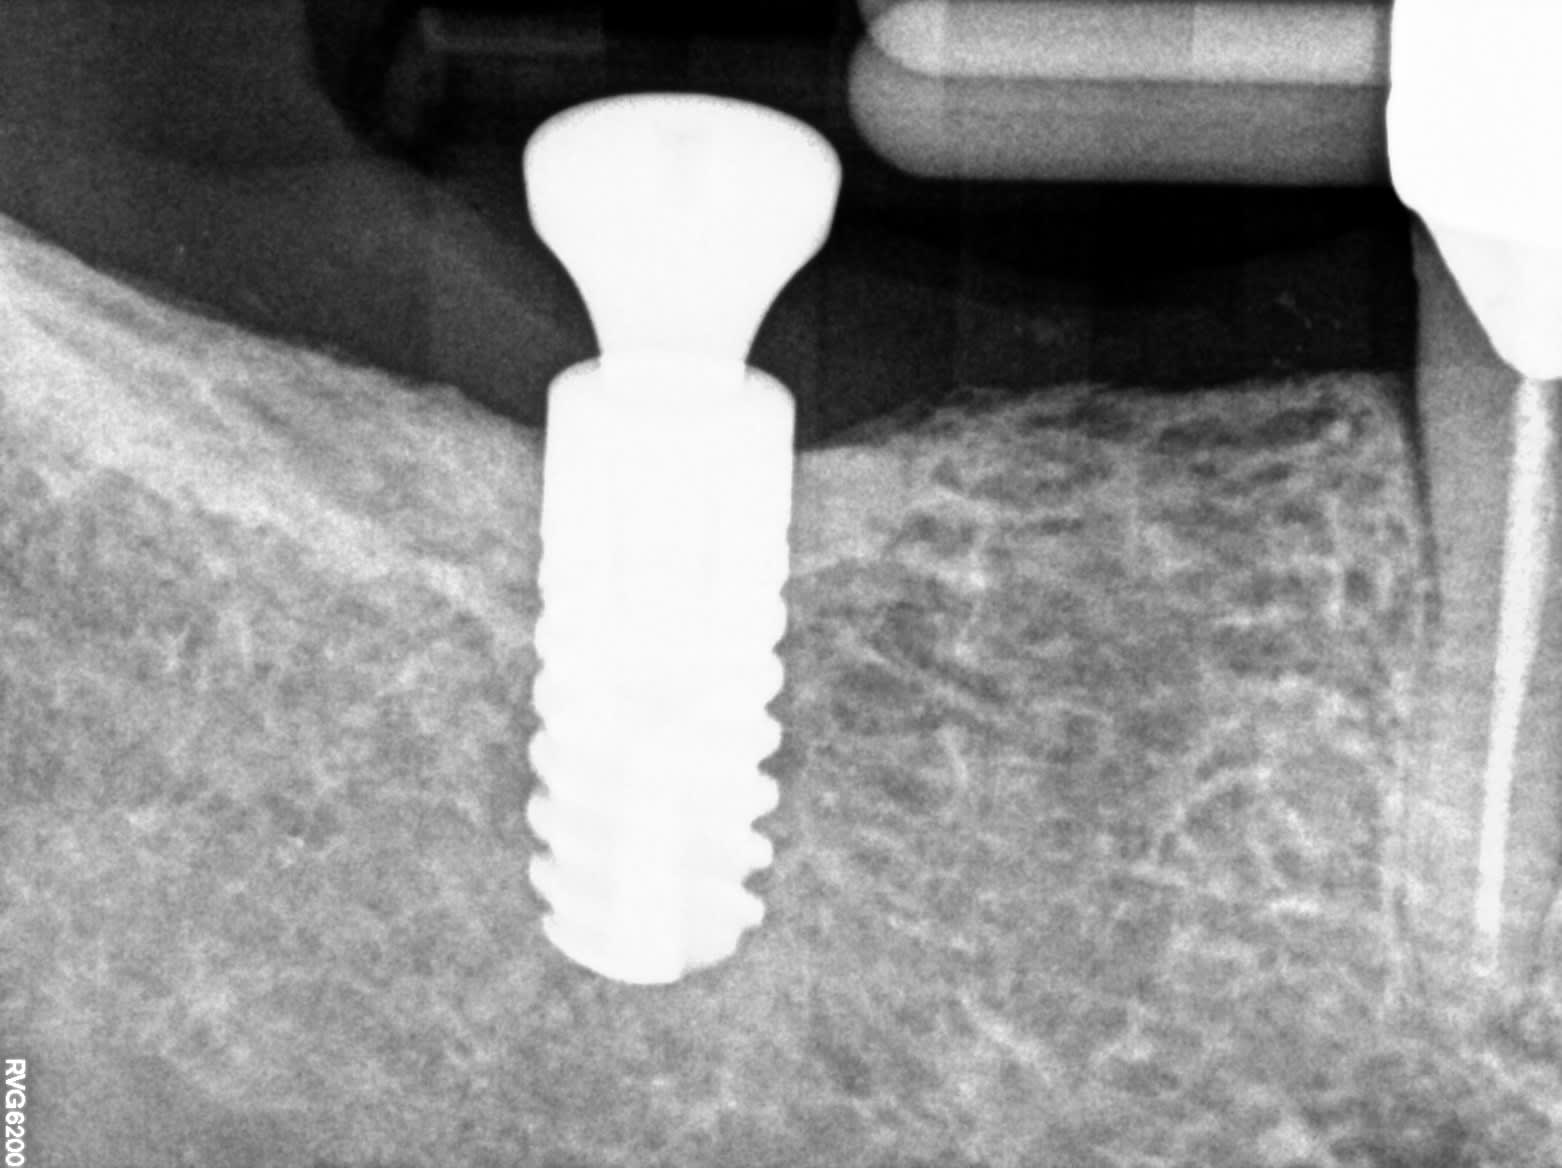

@Pluton, aurais tu celui ci?

Je pense à anthogym AXIOM BL...

ah bah non.....Ankylos....